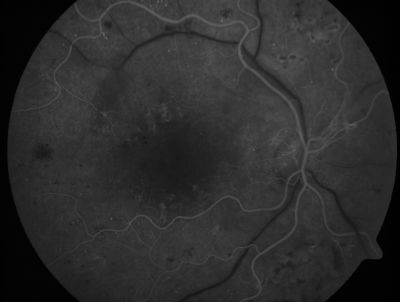

PDR - Mild Vitreous Hemorrhage and Good Vision

58-year-old woman has diabetic retinopathy in both eyes with neovascularization of the optic nerve, worse in the right eye than the left eye.  She has had panretinal laser in both eyes and vitreous hemorrhage in the left eye.  Her vision, since I saw her last in June, is about the same.

VISUAL ACUITY:  Vision OD is 20/25, OS is 20/20.